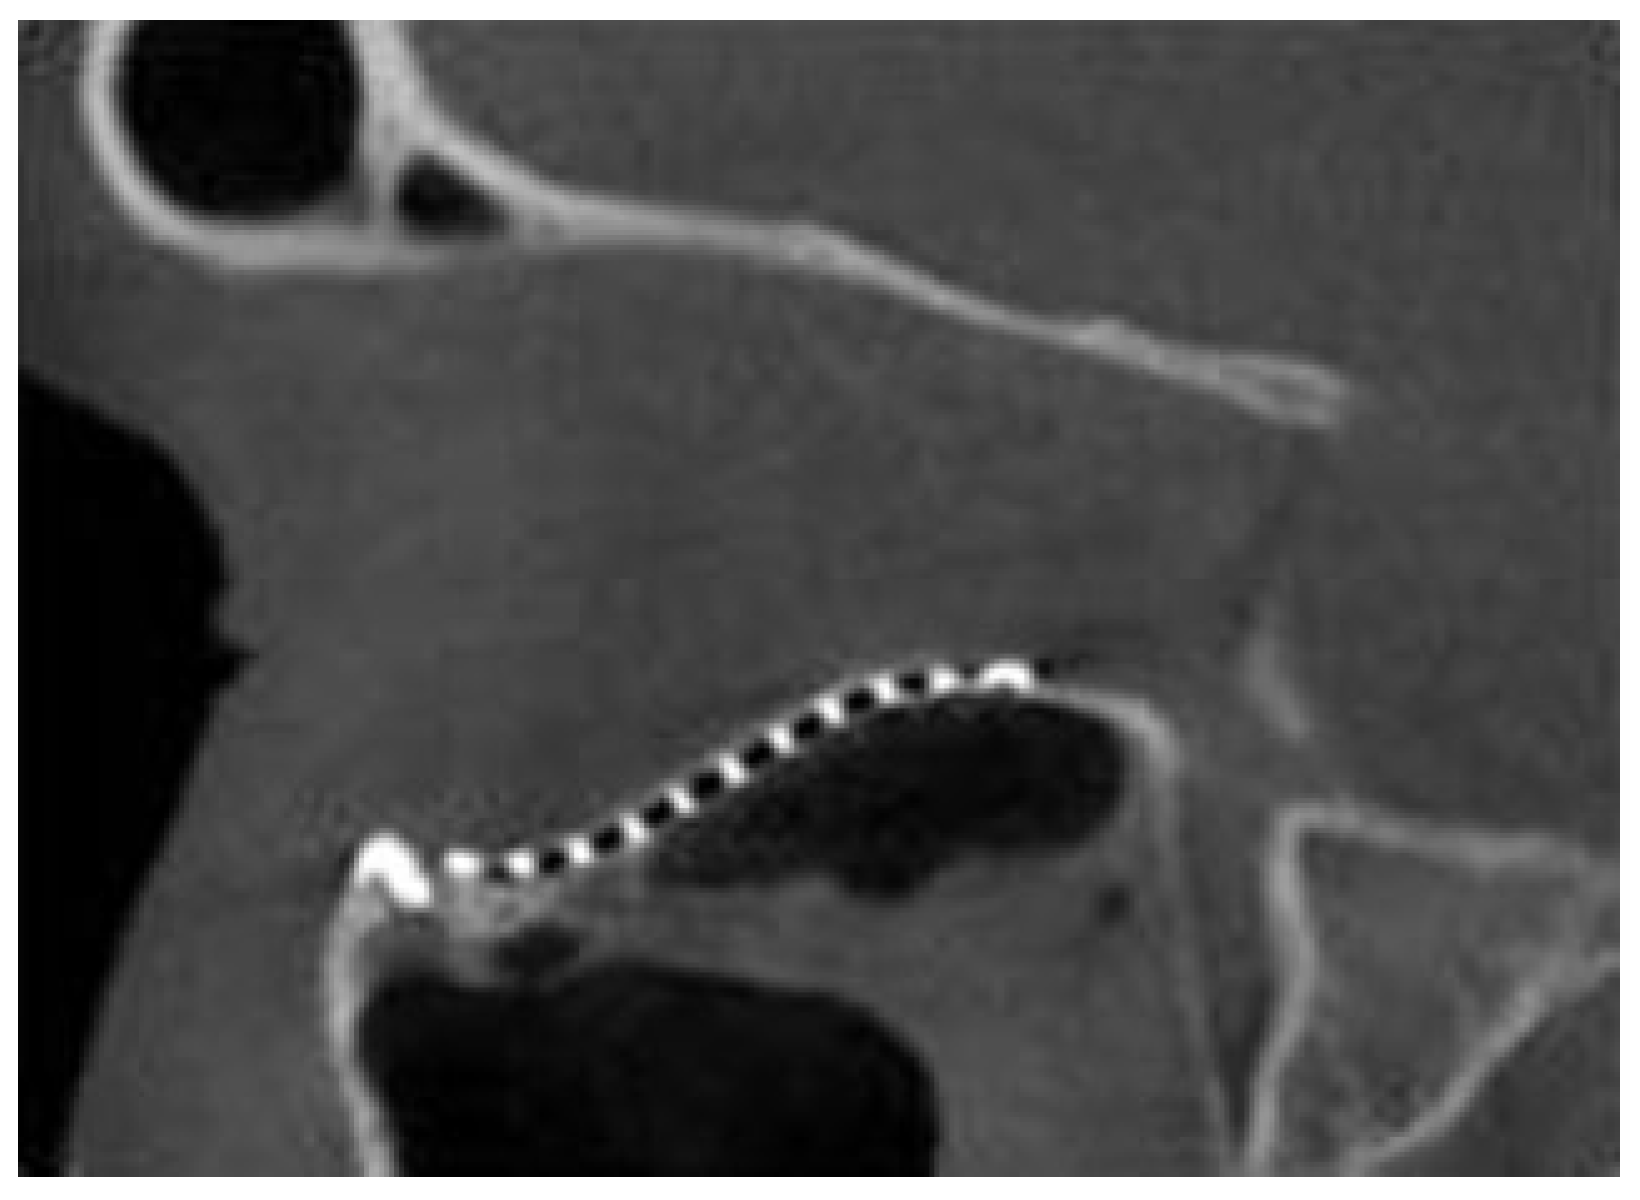

A transconjunctival or subtarsal approach as described by Ellis and Zide[10] was used to access the orbital floor and subperiosteal dissection was undertaken to expose the fracture and its margins. The time was recorded from the moment the operator handled the implant until it was secured with the first screw. An intraoperative CT scan (O-arm, Medtronics, Minneapolis, MN) was used to evaluate the position of the implant and if not positioned optimally, was adjusted and rescanned with an absolute maximum of three scans per patient. The time taken for readjustment was also recorded and totaled to give the “duration of plate placement.” The parameters evaluated were the position of the plate over the posterior ledge, the medial and lateral margins of the fracture (Figure 6), and the anatomical contour in an anteroposterior dimension in regard to restoring the posterior bulge (Figure 7). When an optimal position of the implant was achieved, a forced duction test was undertaken to ensure that the globe was free and a second screw was used for additional fixation. The surgical wounds were then closed. The number of intraoperative CTscans needed was also noted. Intraoperative imaging was occasionally unavailable due to time constraints and facility availability. In these cases, a postoperative cone beam CT (i-CAT, Imaging Sciences International, Hatfield, PA) was used postoperatively within 24 hours to evaluate the implant position.

The time taken for implant positioning and fixation ranged from 4 to 25 minutes (Figure 8). Orbital floor form was assessed radiographically after implant insertion and in all cases found to be flush with the posterior ledge. Furthermore, the reconstructed posterior bulge “key area” was present in all cases.

Figure 7. A sagittal section of an ICAT image demonstrating an orbital implant with optimal anatomical contours which restored the “key area” at the posterior equatorial bulge with the posterior aspect of the implant flush with the posterior ledge.